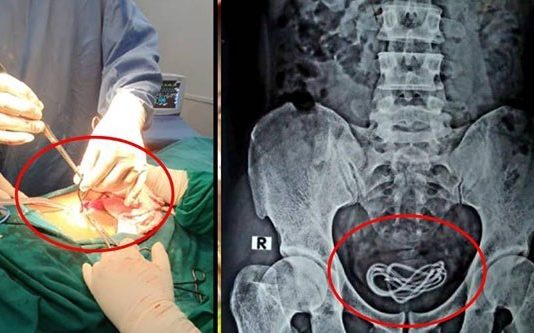

இந்தியாவில் பா லியல் இன்பத்திற்காக இளைஞன் ஒருவர் பிறப்புறுப்பு வழியாக மொபைல் சார்ஜர் கேபிளை செலுத்திக் கொண்டது, மருத்துவர்களிடையே அ திர்சசியை ஏற்படுத்தியுள்ளது.

அசாம் மாநிலத்தை சேர்ந்த 30 வயது மதிக்கத்தக்க இளைஞர், தன்னுடைய...